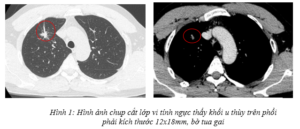

Ca lâm sàng: Phát hiện, chẩn đoán giai đoạn sớm một bệnh nhân mắc đồng thời ung thư phổi và ung thư tuyến giáp tại Trung tâm Y học hạt nhân và Ung bướu, bệnh viện Bạch Mai

Ca lâm sàng: Phát hiện, chẩn đoán giai đoạn sớm một bệnh nhân mắc đồng thời ung thư phổi và ung thư tuyến giáp tại Trung tâm Y học hạt nhân và Ung bướu, bệnh viện Bạch Mai GS. TS Mai Trọng Khoa, PGS. TS Phạm Cẩm Phương, TS. Phạm...